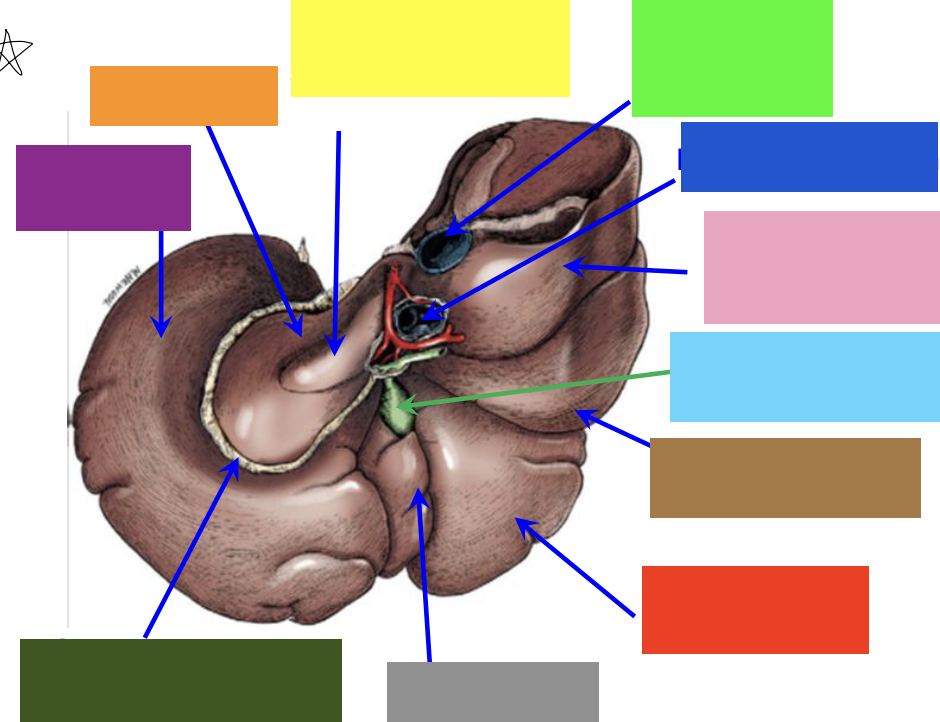

purple box

left lateral lobe

orange box

caudate lobe

yellow box

papillary process of the caudate lobe

neon green box

right lateral lobe

dark blue box

hepatic portal vein

pink box

caudate process of the caudate lobe

light blue box

gall bladder

brown box

right lateral lobe

red box

right medial lobe

grey box

quadrate lobe

dark green box

lesser omentum